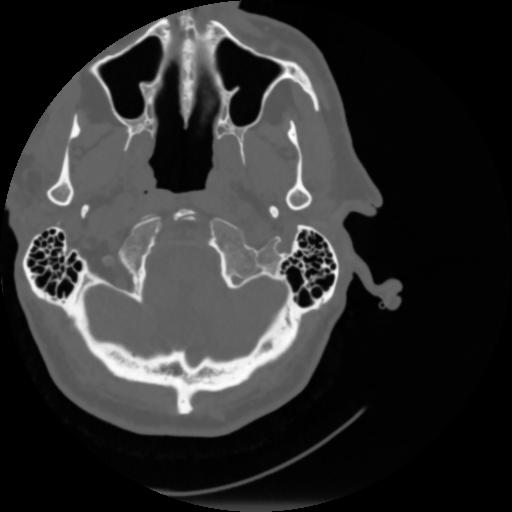

4 CEREBRO,,Vol,0.5,CEREBRO,,